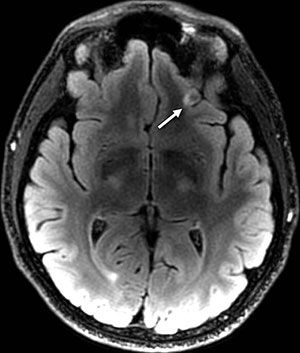

The MRI scans revealed the presence of white matter T2 hyperintensities, which can be thought of as brain scars, in 52 percent of the MTBI patients.

"We were really surprised to see so much damage to the brain in the MTBI patients," Dr. Riedy said. "It's expected that people with MTBI should have normal MRI results, yet more than 50 percent had these abnormalities."